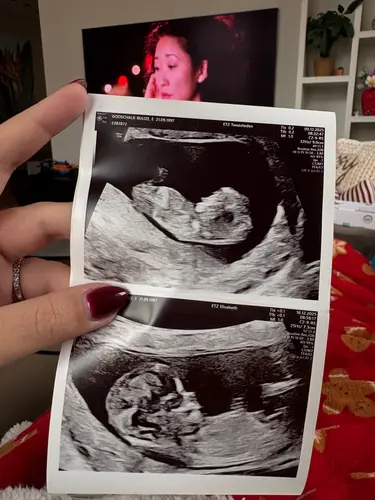

Nu ben ik ook nog geen 13 weken, ik ben 12+4 vandaag. Maar werd automatisch ingepland. Had vorige week mijn termijnecho.

Stond er van te kijken hoe groot het verschil was tussen een week geleden en nu.

Bovenste was vorige week. Onderste nu